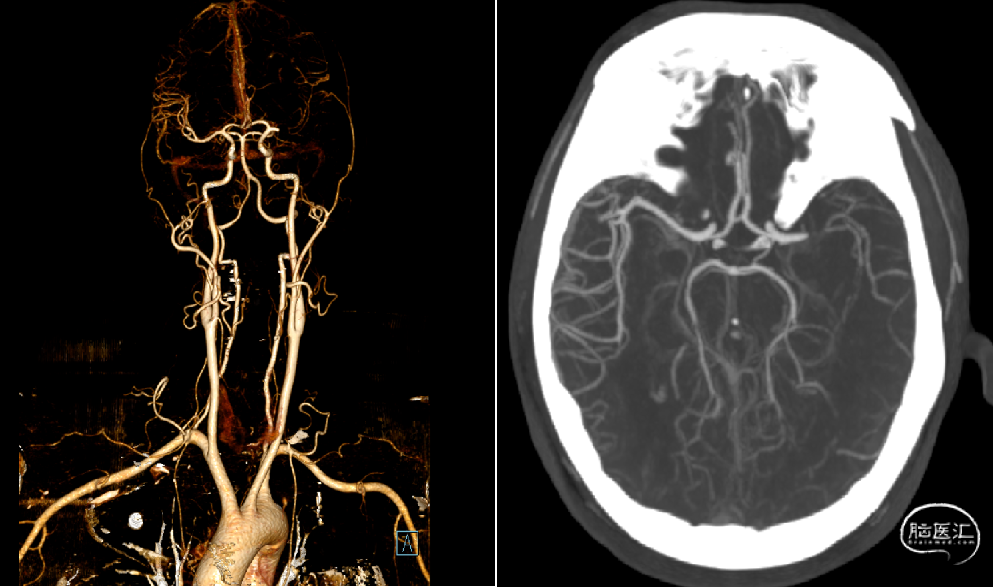

患者为急性脑梗死,在当地医院已行阿替普酶静脉溶栓,溶栓后病情好转,后再次加重,入院后复查头颅CT未见出血,急诊头颈部CTA提示左侧大脑中动脉闭塞,考虑左侧大脑中动脉重度狭窄基础上急性血栓形成,患者年轻,CTA时相可见侧枝代偿丰富,目前病情进展加重,有急诊取栓指征。

造影显示左侧大脑中动脉闭塞,右侧颈内动脉及后循环血管未见明显异常;左侧大脑前动脉通过软膜支部分代偿。